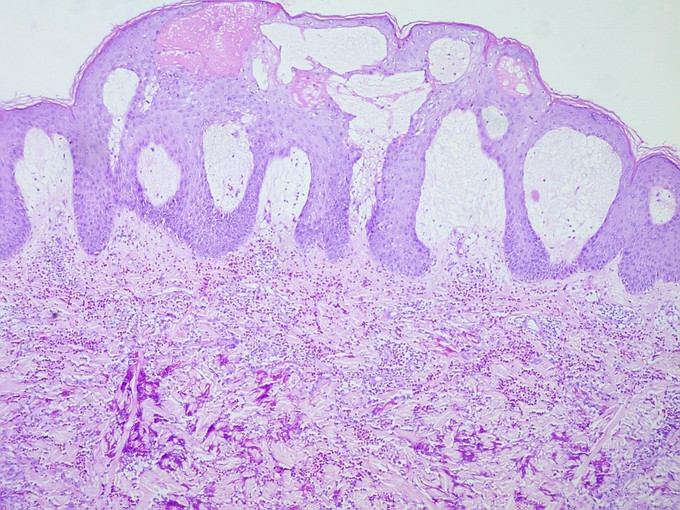

体格检查:系统检查无异常。皮肤科检查:右上肢弥漫性红肿,非可凹性,皮温高,触之较硬。双手、右前臂散在粟粒至黄豆大小水疱、大疱、脓疱,尼氏征阴性,左前臂、双足跖有少量大小不一黄色结痂面。四肢、背部、腹部多发大小不一、境界欠清之色素沉着斑。 实验室及辅助检查:血常规WBC 15.84×10*9/L,EOS% 20.4%,EOS 3.88×10*9/L 。疱液细菌培养及真菌培养均未见异常。ANA、dsDNA,、ENA谱均阴性。组织病理检查:表皮棘层不规则肥厚,皮突延长,真皮乳头高度水肿,真皮全层和皮下脂肪可见大量嗜酸性细胞浸润,并可见火焰现象。

嗜酸性蜂窝织炎(Eosinophilic Cellulitis)是一种以反复发作的红色水肿性斑块为特点的疾病,最早由Wells于1971年首先报告,又称Wells综合征(Wells syndrome)。本病发病无性别差异,患者年龄跨度大,平均37岁。疾病在发病早期类似于急性蜂窝织炎,皮肤病理表现为显著的炎症性肉芽肿特征。皮损好发于四肢和躯干。常表现为边界清晰、水肿性、触之坚实的环状红色斑块,类似蜂窝组织样,但也可有其他多种临床表现,包括水疱、结节、丘疱疹和瘙痒性剥脱性炎性丘疹。有些患者可引起疼痛和瘙痒,皮损愈后不留瘢痕。 本病病理变化:急性期皮损活检可见真皮水钟,并有大量的嗜酸性粒细胞浸润,表皮下偶见水疱。亚急性期真皮有弥漫性组织细胞和嗜酸性粒细胞浸润,部分碎裂的嗜酸性粒细胞围绕着坏死的胶原纤维形成斑块状浸润,可以见到大而淡染的组织细胞及异形巨细胞围绕嗜酸性不定形物呈栅栏状排列的“火焰像”。消退期组织细胞渐进性坏死,类似肉芽肿的改变,仍有“火焰像”持续存在。根据患者的临床特征及病理上“火焰像”的特点可诊断本病。本例患者起病时皮疹不典型,开始时为单侧发病,表现为红色小丘疹、后逐渐形成水疱、大疱,故曾被诊断为“带状疱疹”,皮损进展到对侧上肢并出现脓疱后又被诊断为“掌跖脓疱病”,最终取皮肤病理而确诊。 本病发病原因的机制尚不清楚。部分患者血清中可以出现抗核抗体,组织病理上可见广泛发生的纤维蛋白样坏死,小血管炎及嗜酸性粒细胞增多,故认为可能为自身免疫性疾病,本病是否是原发性独特的疾病还是对其他可能的过敏刺激的反应还不清楚。它与昆虫叮咬、盘丝虫病、肠道寄生虫病、水痘、腮腺炎、破伤风疫苗接种、药物反应、骨髓增生症、特应性素质、嗜酸性粒细胞增多综合征和真菌感染有关。 本病对抗生素治疗无反应,该患者曾使用“头孢类抗生素”治疗无效也印证该点。有效的治疗包括口服抗组胺药、氨苯砜或小剂量激素,UVB或PUVA也可能有效。本患者经小剂量激素治疗后病情有改善,目前仍在随访中。